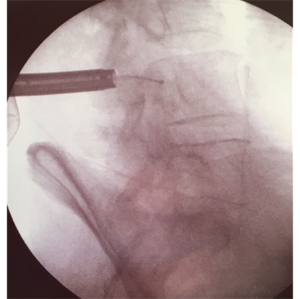

Intra-operative X-ray image showing the endoscopic cannula (left) out of which a radiofrequency electrode runs out (small ball at the tip) across the spinal canal. This proves that the spinal canal has been decompressed and the the release of the dura.